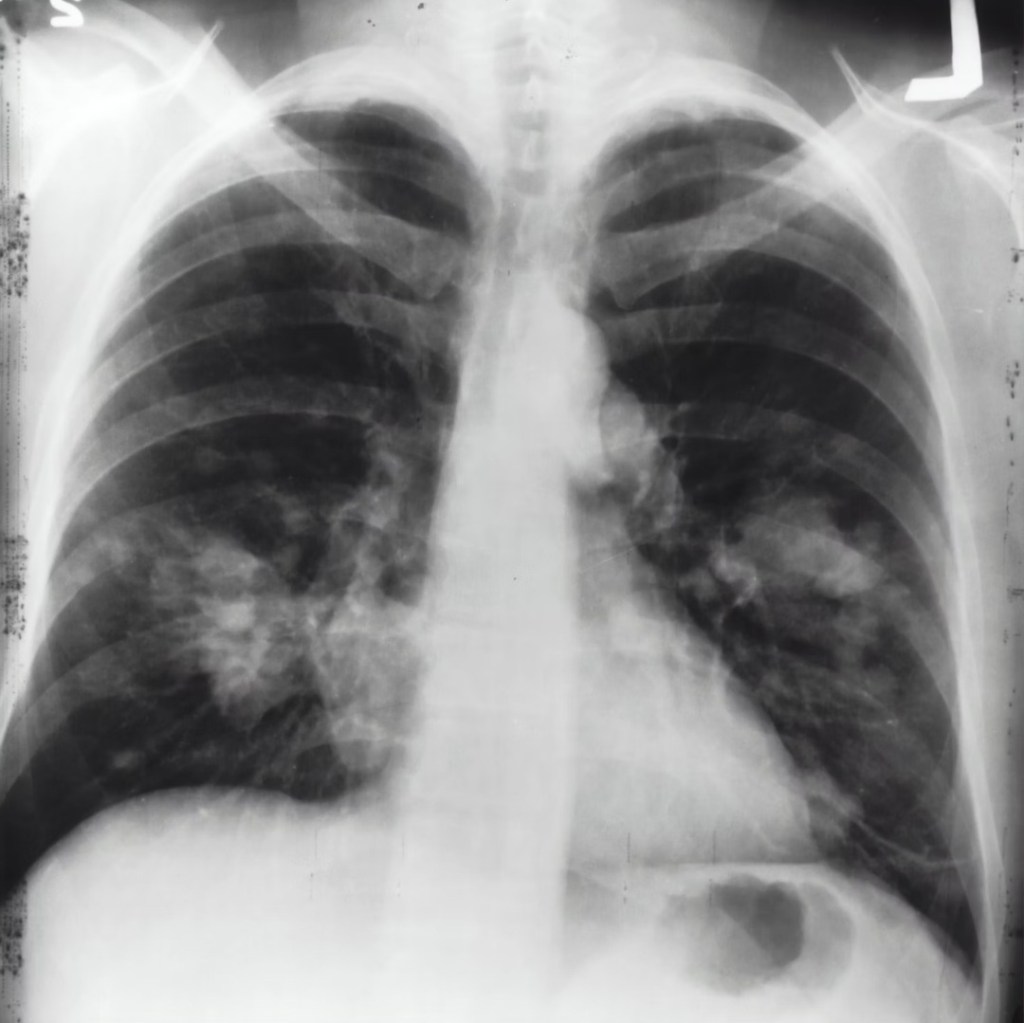

Radiographic findings, such as irregular lung opacities and pleural thickening, aid in the diagnosis of asbestosis. The severity is directly linked to the cumulative asbestos exposure.